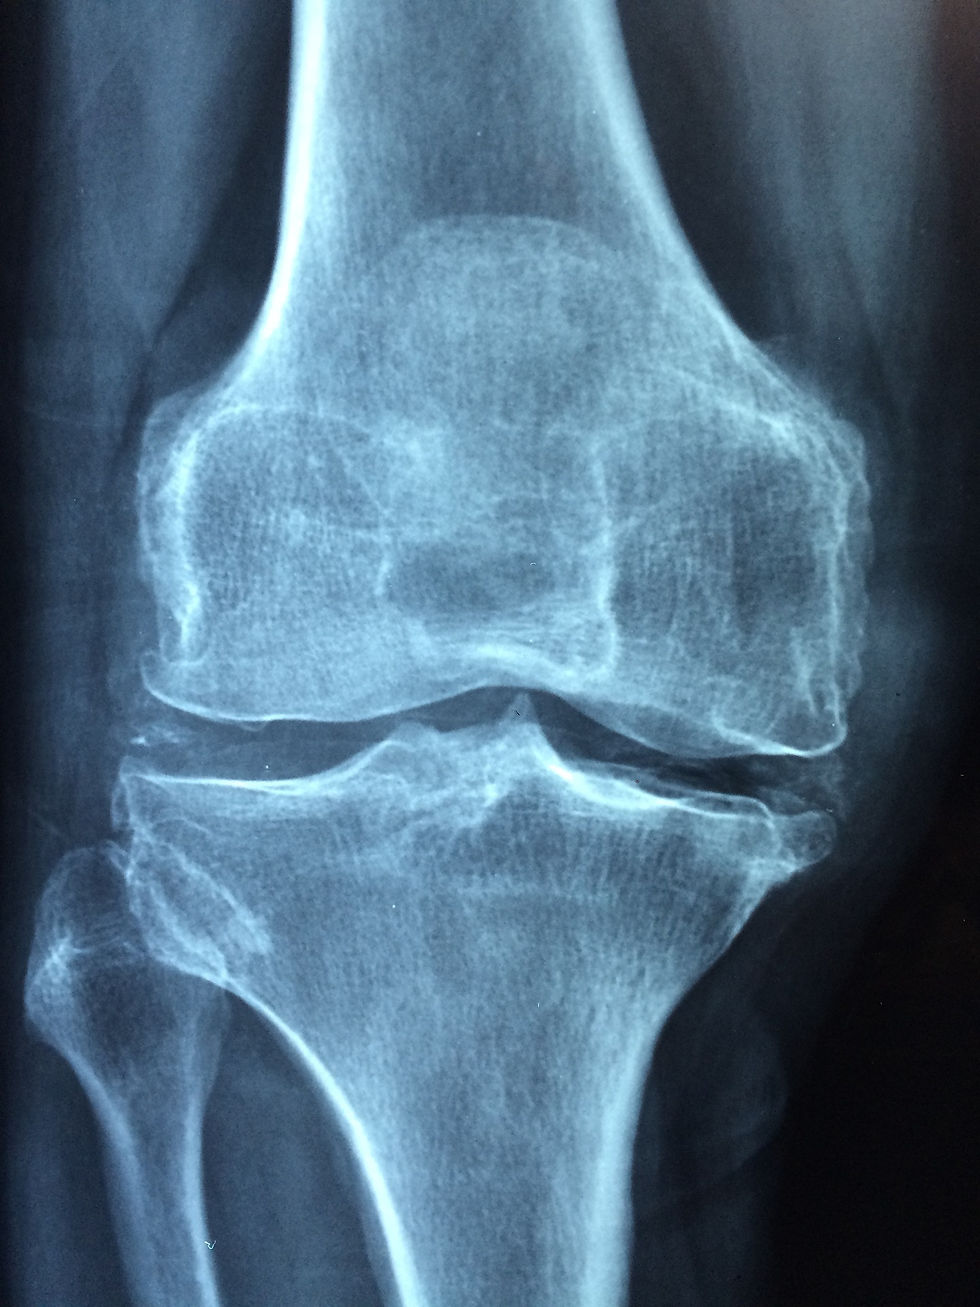

Arthritis is defined as inflammation of one or more of your joints. Pain, swelling, and stiffness are the primary symptoms of arthritis. Although any joint in the body may be affected by the disease, it is particularly common in the knee.

Osteoarthritis is the most common form of arthritis in the knee and is basically a "wear-and-tear" type of arthritis that occurs most often in people 50 years of age and older.